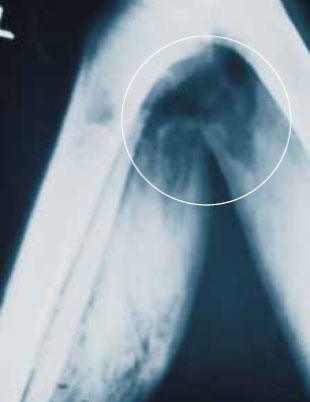

Следует помнить, что пузырьки воздуха, видимые на рентгенограмме, не обязательно свидетельствуют о выделении газа вследствие воспаления скелетных мышц. Временная полость, образующаяся при ранении высокоскоростными пулями, нередко оставляет за собой пальпируемый и видимый на снимках внутрифасциальный и внутримышечный воздух в здоровых тканях на некотором удалении от раны. Это обычно является показателем тяжелого повреждения тканей. Диагноз газовой гангрены делают на основе клинических симптомов, и рентгенография не является для него патогномоничной (рисунок 2).

Рисунок 2. На рентгенограмме определяется воздух в ткани пациента, у которого нет газовой гангрены